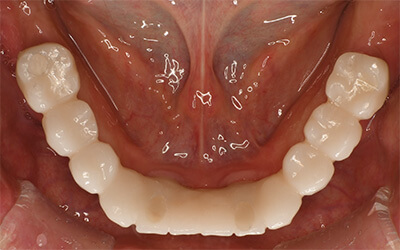

【歯周病で多数歯欠損②】とにかく入れ歯をやめたい!上オールオン6・下オールオン4の患者様

患者さま情報:40代 男性

治療期間:11ヶ月

治療費:5,082,000円(税込)

リスク:骨が足りない場合は骨を足す骨造成が必要です。

副作用:手術により腫れや痛みを伴う場合があります。

before

after